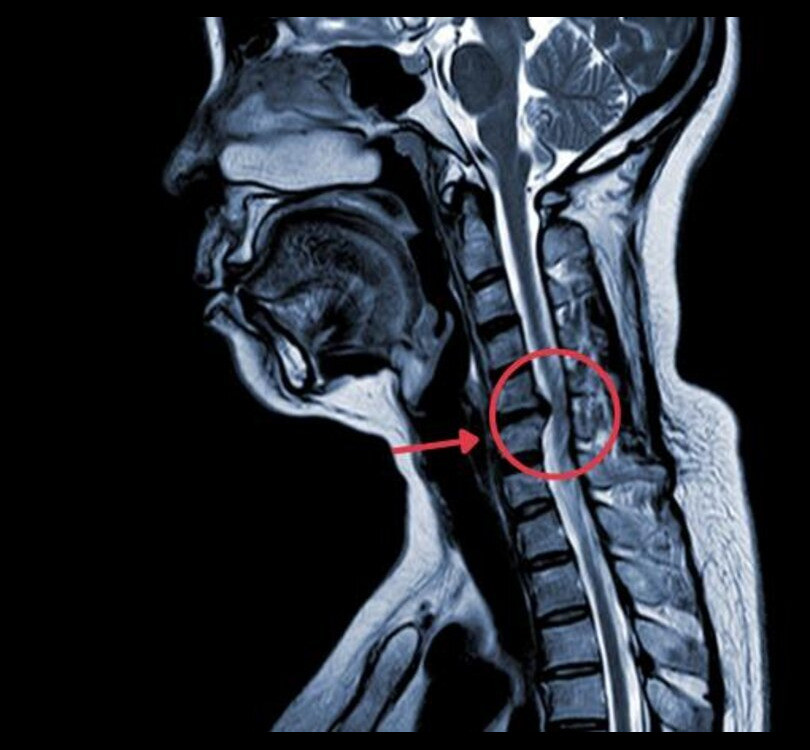

Imaging Tests

Imaging tests, such as MRI or CT scans, are used to visualize the spine and identify any compression or damage to the spinal cord.